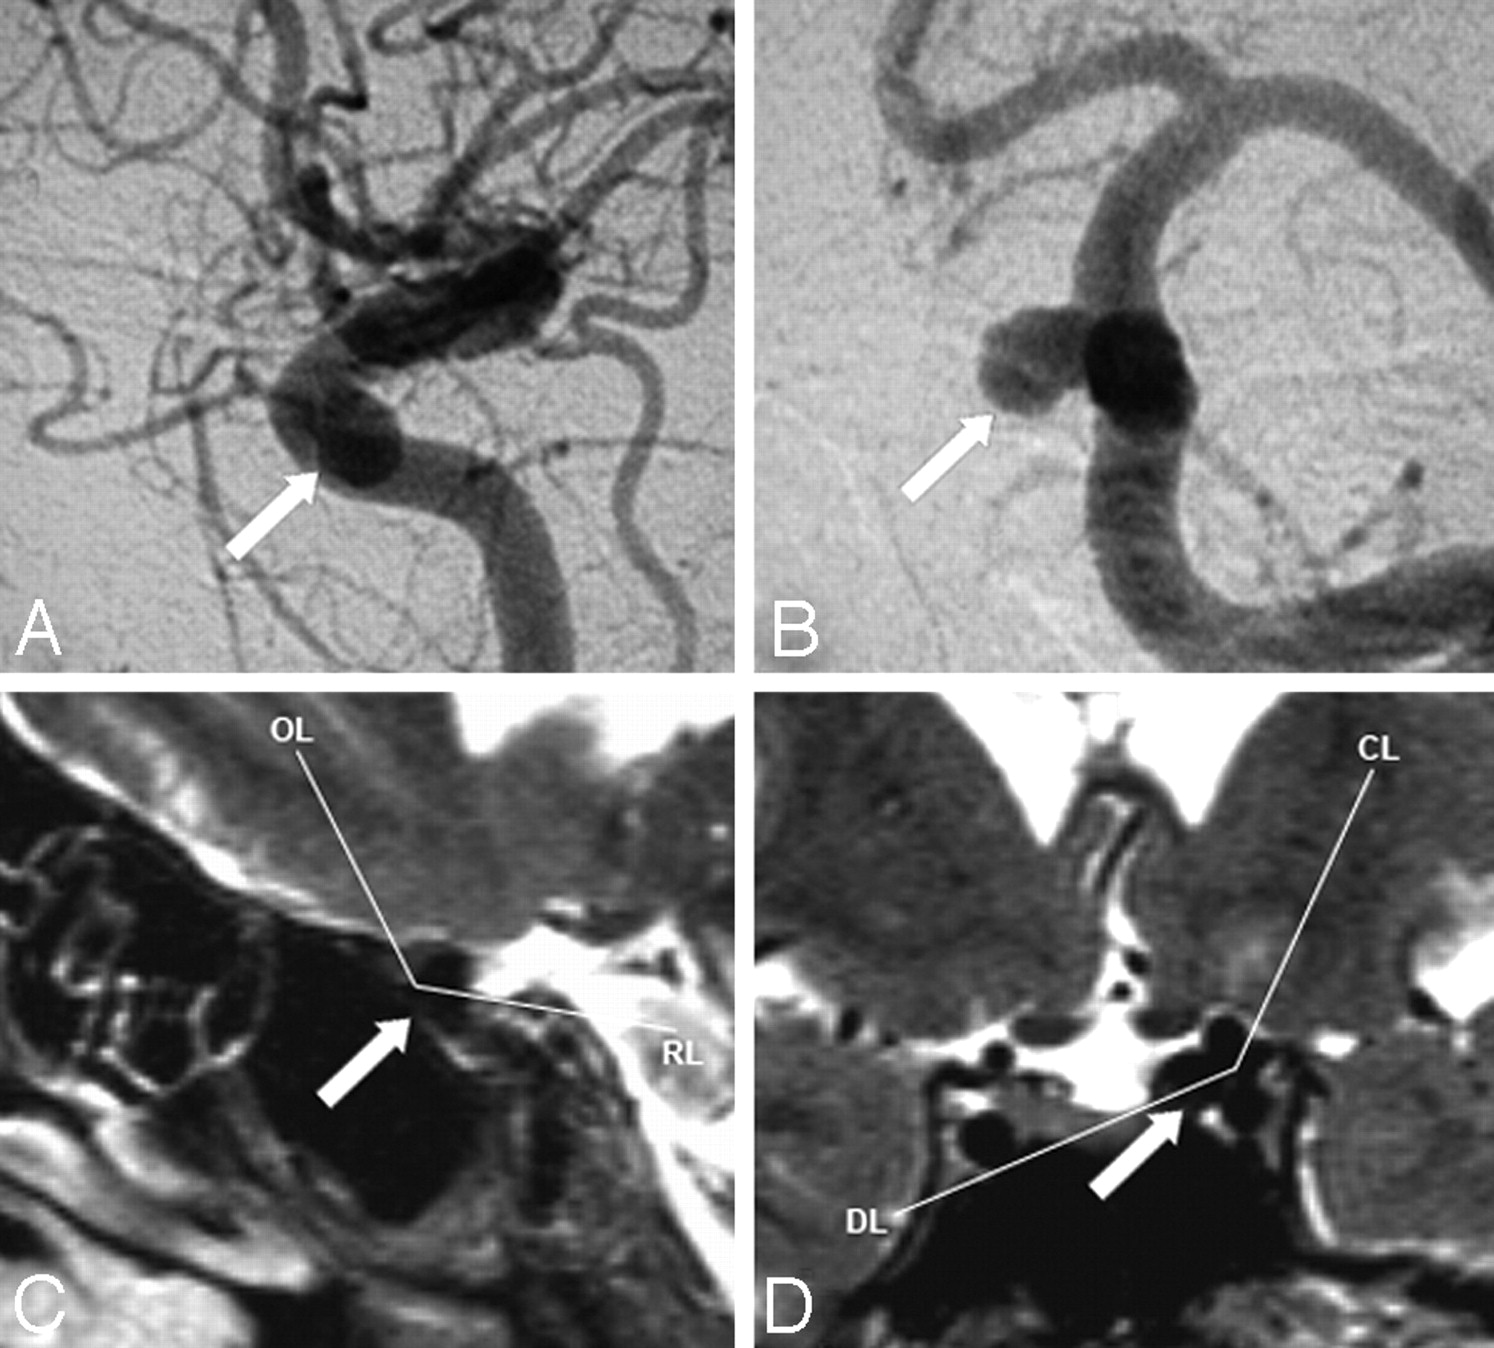

Comparison between angiogram and PMP for the location of case 2 (arrows). Both examinations show an intracavernous aneurysm (neck and sac intracavernous). A, DSA of the left ICA in the lateral view. B, 3D-DSA of the left ICA in the anterior view. C, PMP in the carotid plane (OL indicates optic line; RL, roof line). D, PMP in the diaphragmatic plane (DL indicates diaphragmatic line; CL, clinoid line).

Comparison between angiogram and the PMP for the location of case 13 (arrows). Both examinations show a transitional aneurysm (neck intracavernous and sac transitional). The PMP depicts a widest supracavernous portion than it is suspected on initial DSA. A, DSA of the left ICA in the lateral view. B, 3D-DSA of the left ICA in the anterior view. C, PMP in the carotid plane (OL indicates optic line; RL, roof line). D, PMP in the diaphragmatic plane (DL indicates diaphragmatic line; CL, clinoid line).